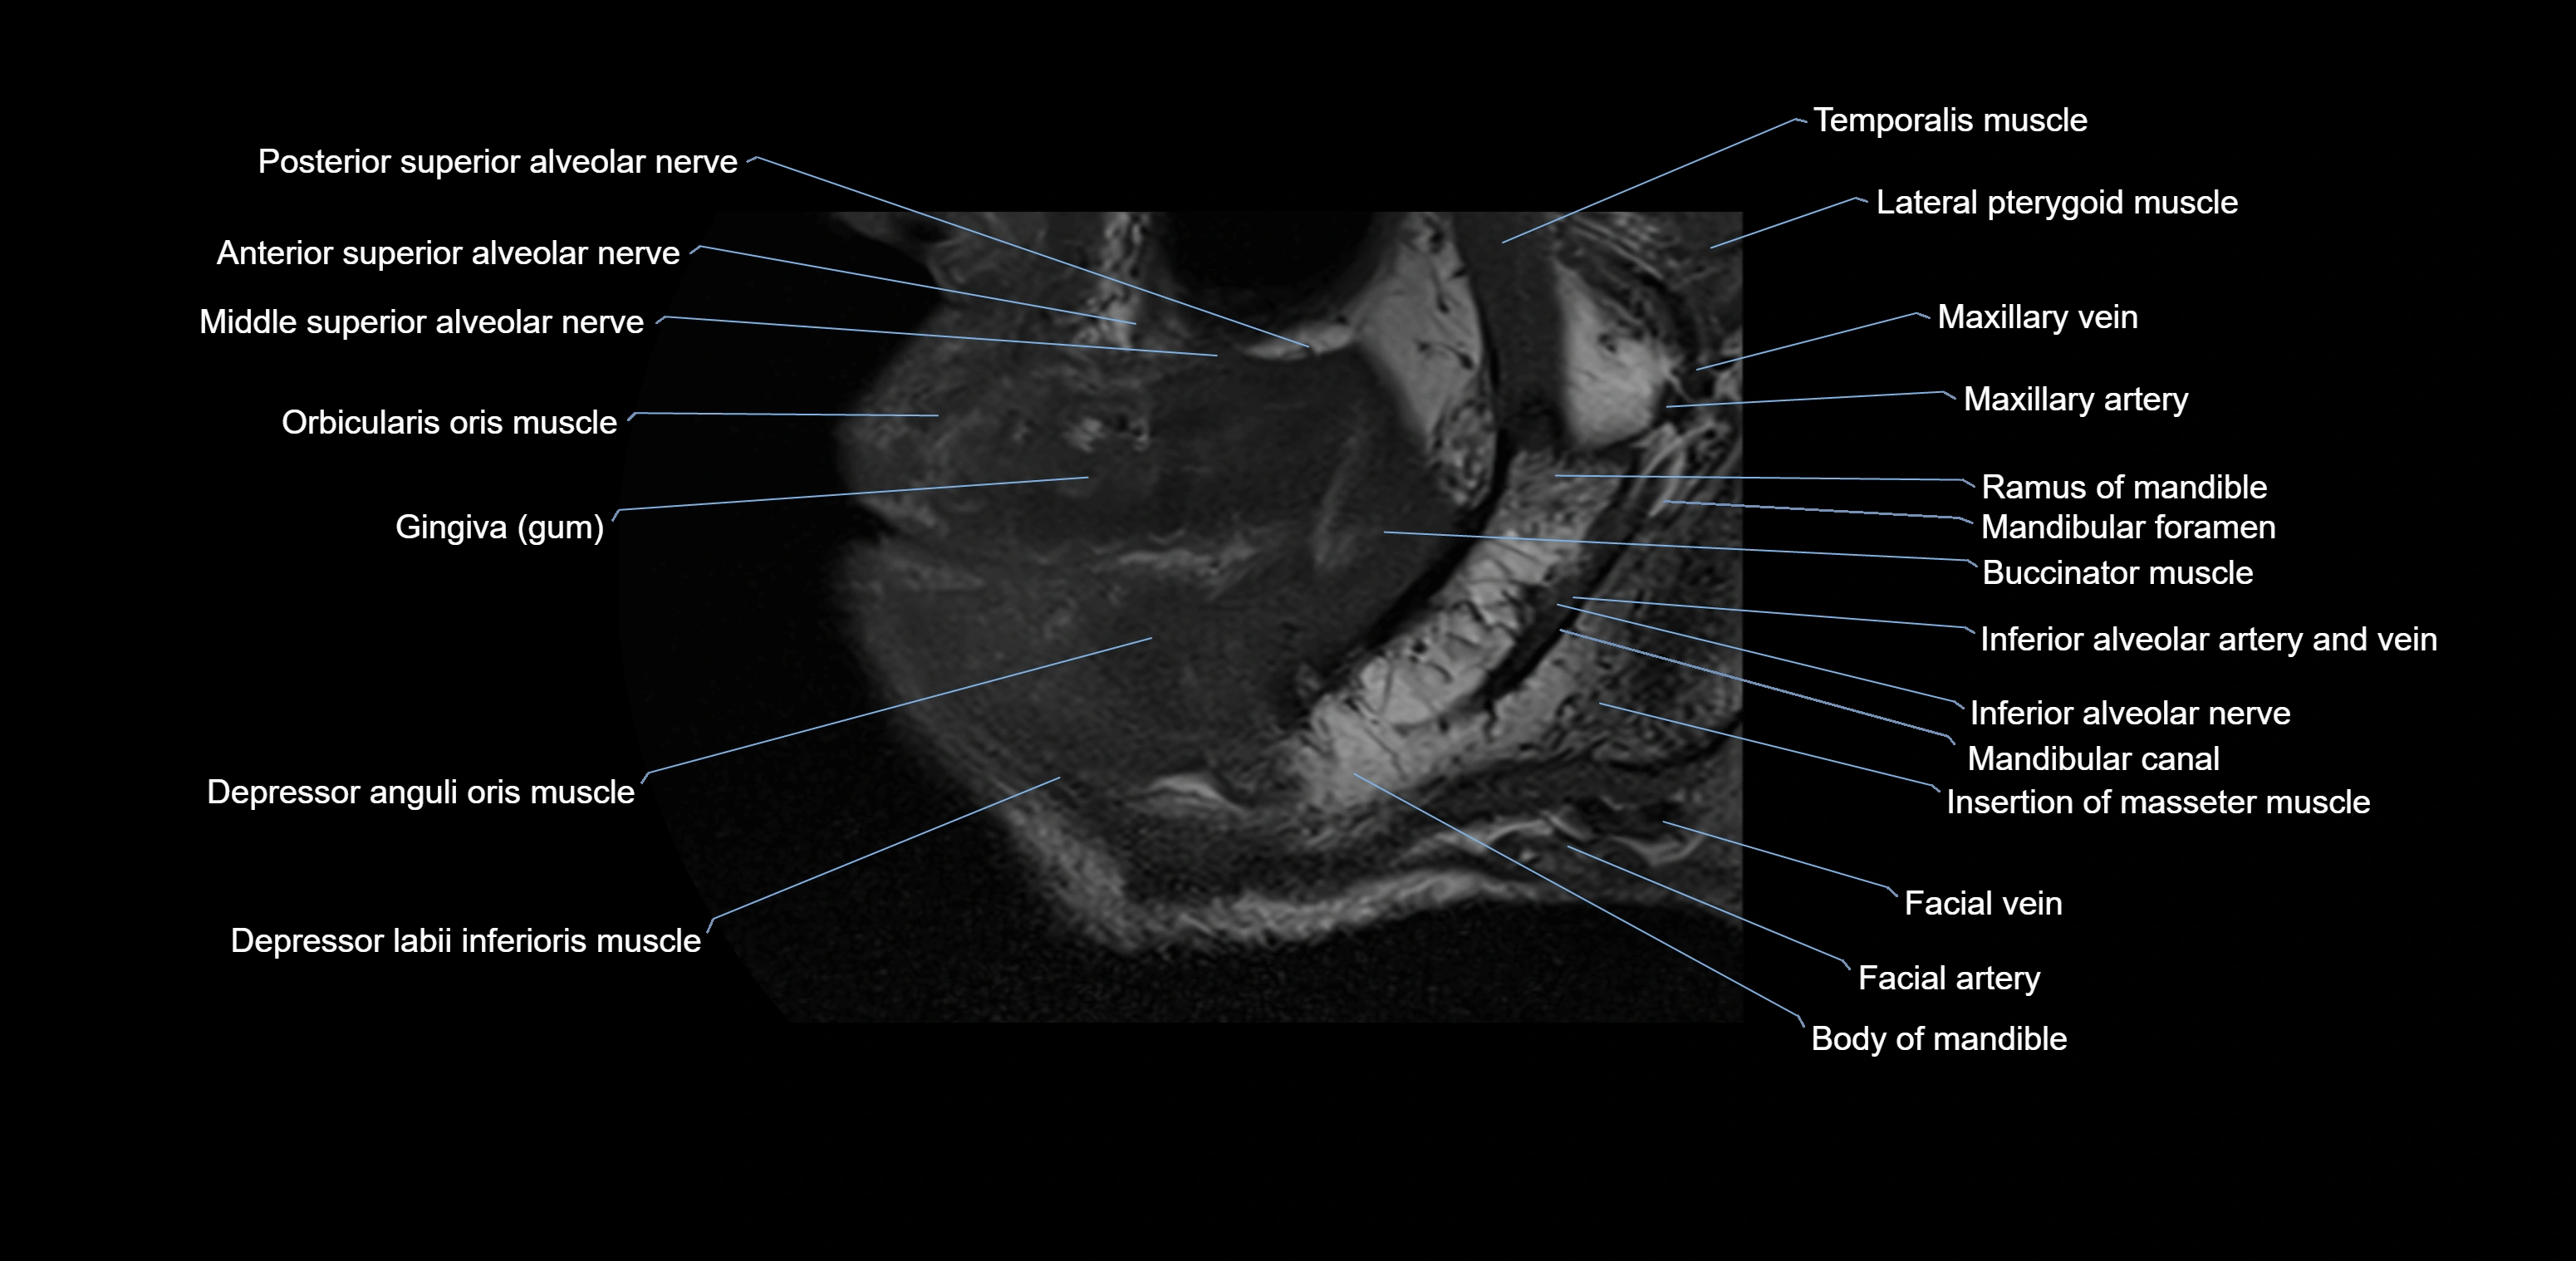

- Anterior superior alveolar nerve

- Buccinator muscle

- Inferior alveolar nerve

- Mandibular canal

- Mandibular foramen

- Middle superior alveolar nerve

- Orbicularis oris muscle

- Posterior superior alveolar nerve

- Ramus of mandible